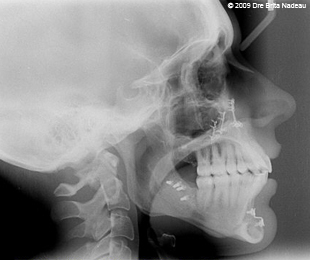

- Introduction

- Guide de l'opéré

- Mon histoire

- Photos & radiographies